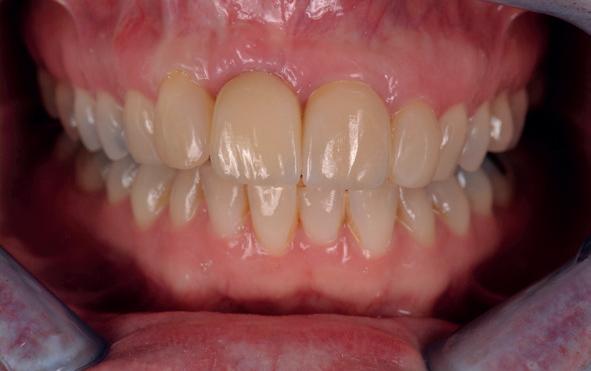

1. Studiofoto intake

aan zijn gebit gedaan behalve pappen en nathouden. Tandheelkundige zorg werd enkel verleend wanneer er zich een probleem voordeed (afbeelding 1, 3, 5).

Na afronding van de eerste twee behandelstappen werd parodontale stabiliteit bereikt, zoals waarneembaar op de parodontiumstatus en (röntgen)foto’s (afbeelding 6, 8). De patiënt toonde aantoonbare verbetering in mondhygiëne (afbeelding 4) en bleef gemotiveerd om de behandeling voort te zetten.